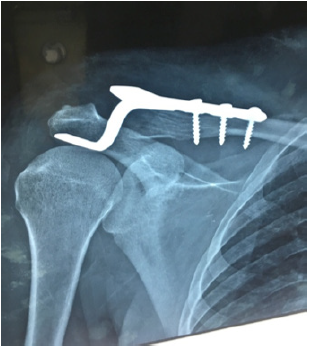

A total of 22 patients were included in this study, who were treated from April 2016 to March 2019 at the Department of Orthopaedic and Spine surgery Hayatabad medical complex and Khyber Medical Centre Dabgari Garden Peshawar. After acquiring an informed consent from the patients and proper pre-operative evaluation and preparation, the patients were operated on under general anaesthesia. Local aesthetic and adrenaline were used in the wound site to aid in minimizing per-operative bleeding. After properly exposing and reducing the fracture, the hook plate was slid under the posterior aspect of the acromion, pressing the plate and aligning it with the clavicle on superior surface and fixed. The average time period of the procedure was around 35 minutes with about 200ml of blood loss. The usual post-operative routine was to keep the patient’s arm in a polysling for two weeks and then start exercise gradually. The follow-up time period ranged from a minimum of 6 months to a maximum of 3 years post-operatively (Figure 2).

Figure 2:United lateral third fracture with hook plate.